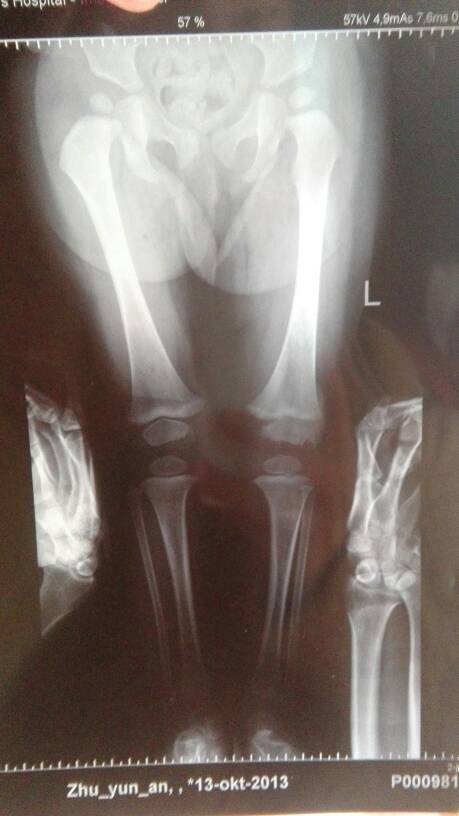

宝宝十五个月,走路早,现在走路左腿明显弯,还有点内八字,担心是不是螺旋腿?内八字把鞋对换着穿行吗? 宝宝十五个月,走路早,现在走路左腿明显弯,还有点内八字,担心是不是螺旋腿?内八字把鞋对换着穿行吗? 点击展开 Lㄡeヱoヴ Me 2015-01-08 13:02 为您推荐: 其他回答 听过这样的,试下了 乖乖浩宝宝 2015-01-08 13:25 相关问题 宝宝十一个月了,发现站着的时候严重的外八字,扶着迈步也是八字往前迈,以后宝宝要是这样走路该多愁阿 宝宝一岁有轻微的内八字怎么办了?穿什么鞋好啊 内八字和外八字都可以用穿反鞋的方式纠正吗?